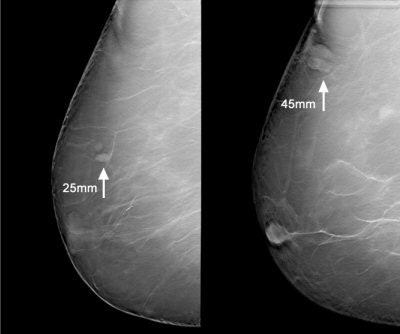

![]() |

| Left, mammogram shows very subtle architectural distortion (arrow). Right, magnification views shows mass, which is still very subtle (arrow). Images courtesy of Joseph Lo, Ph.D., Duke University Medical Center, Durham, NC, and Siemens Medical Solutions. |